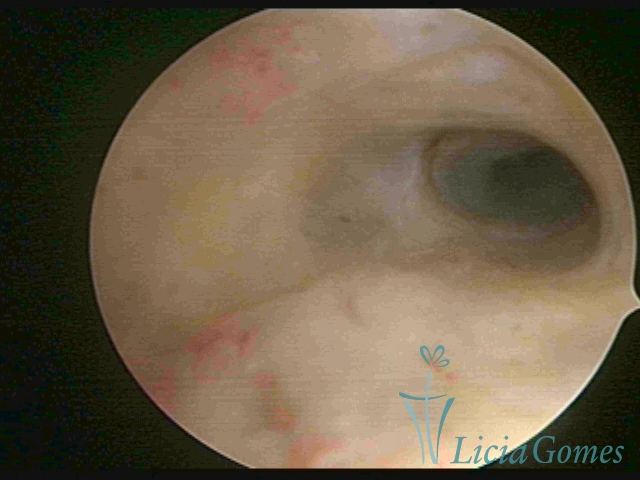

Second part or middle section

In the middle section of the cervical canal, the details of the buds are lost. It is possible to view creases and crypts. Longitudinal grooves are frequently observed. They are the most compact tissues presenting the most vascularized surface, whose vessels follow its passageway.